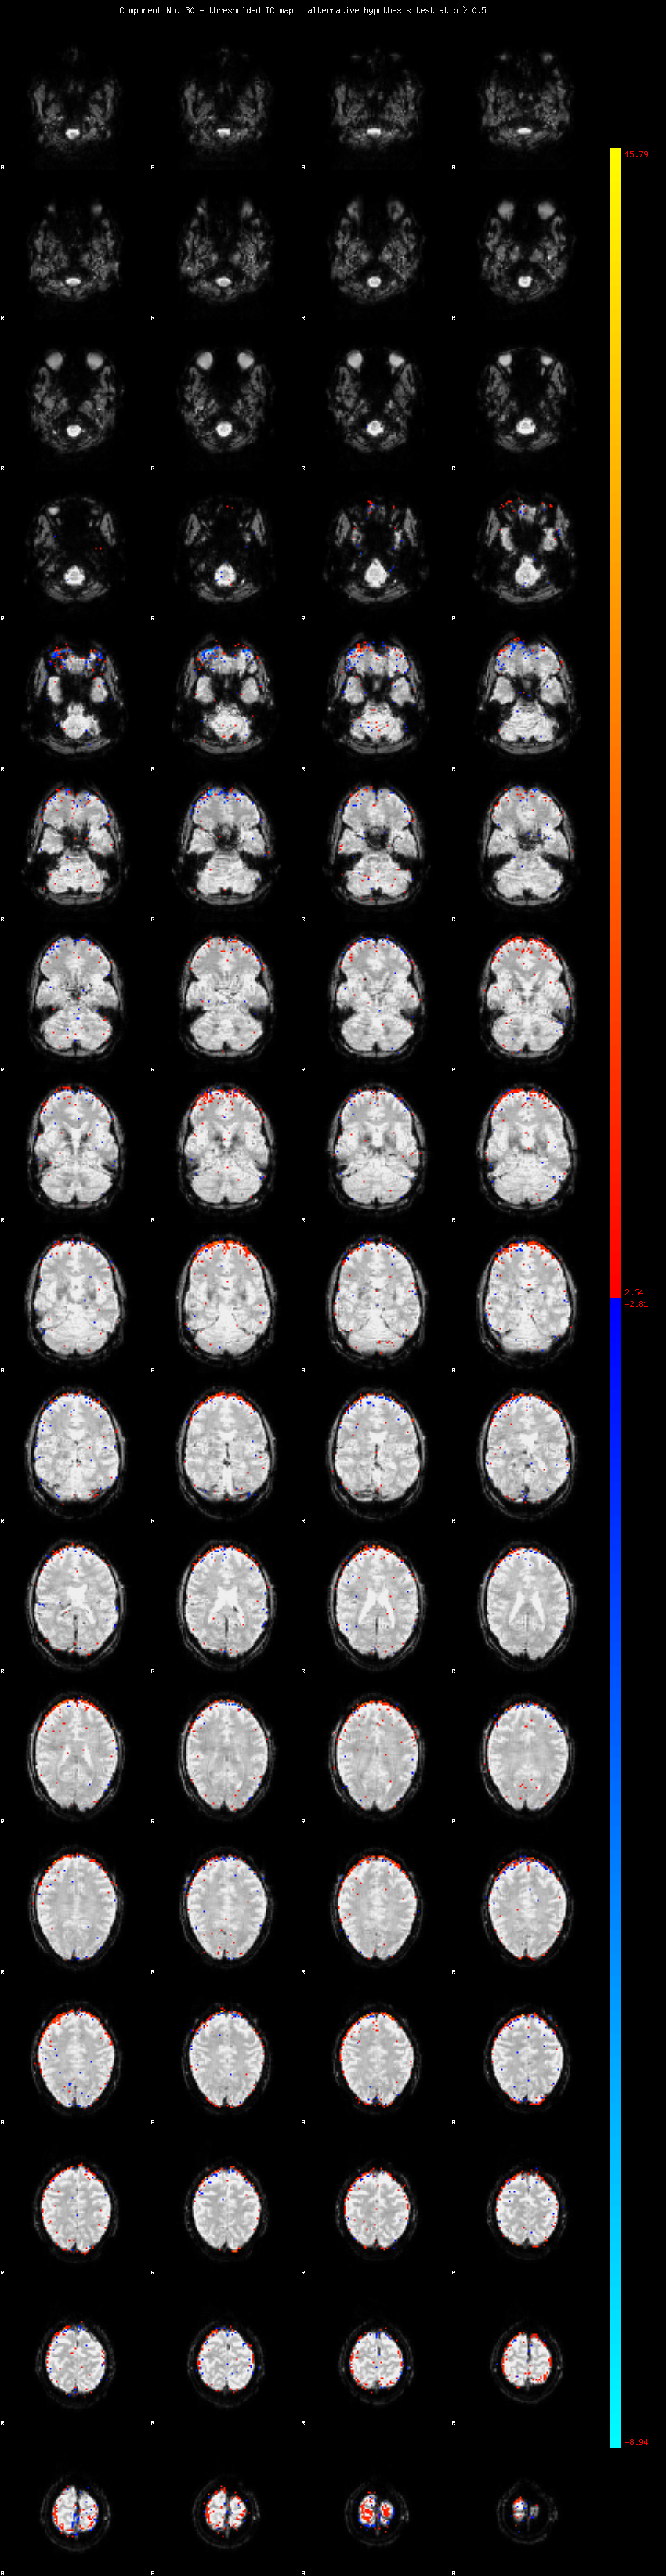

MELODIC Component 30

1.23 % of explained variance;     0.81 % of total variance

MMfit